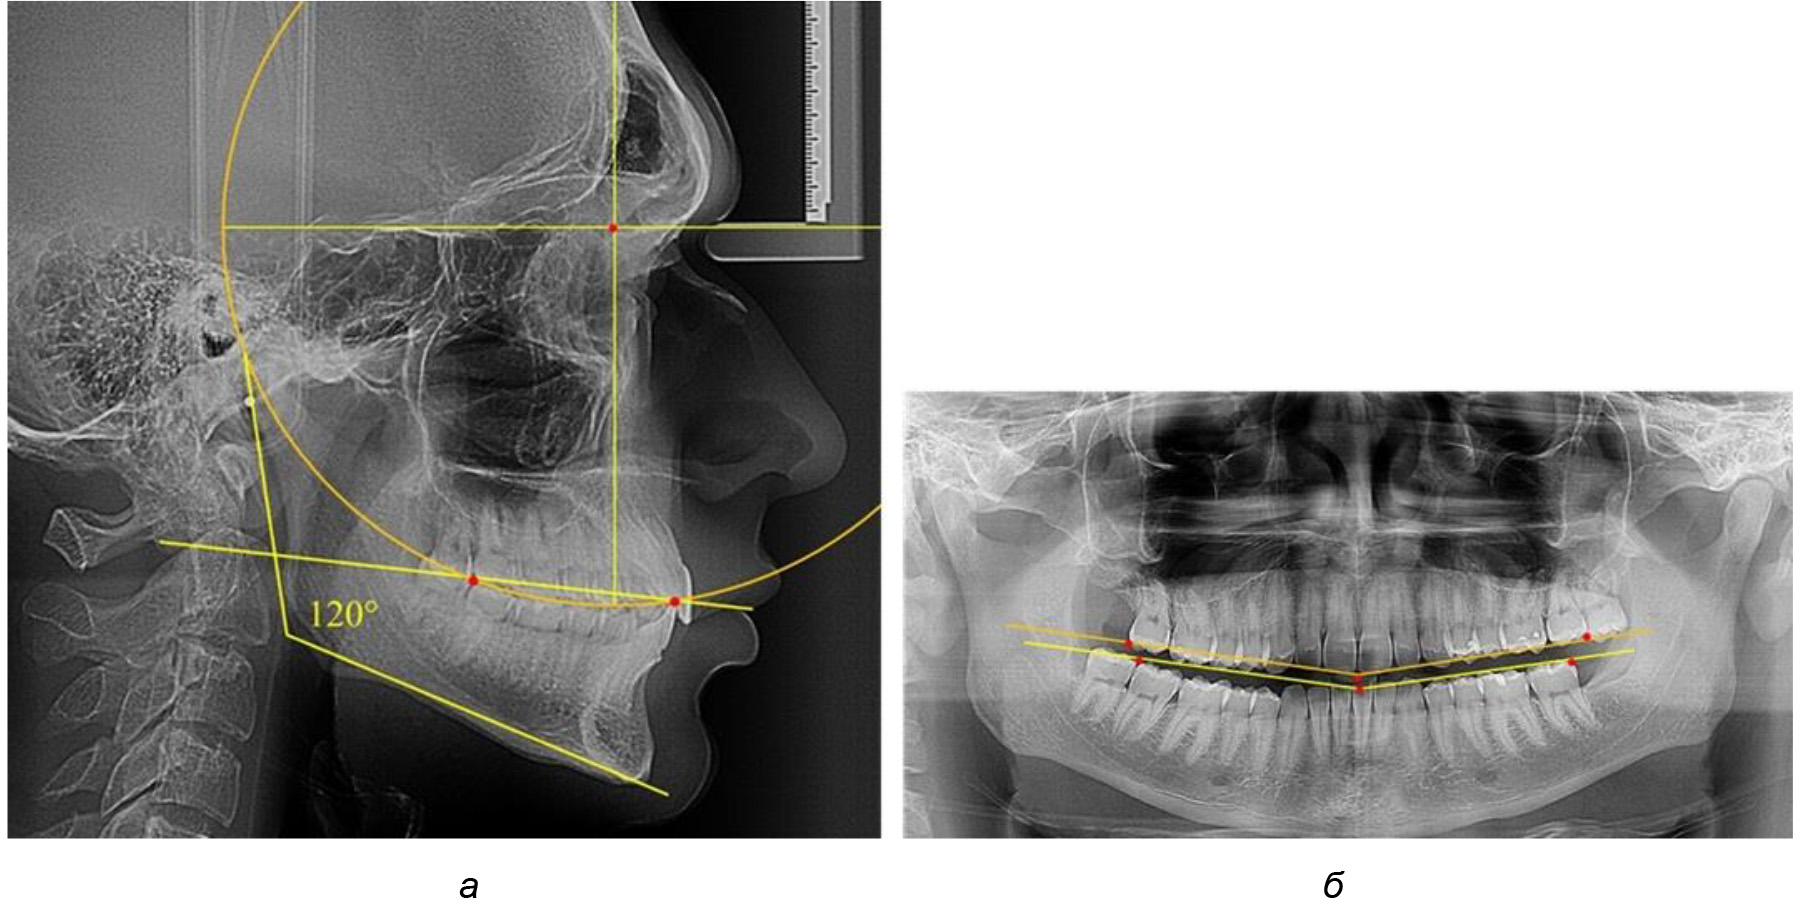

При анализе латеральных ТРГ устанавливали реперный окклюзионные точки в переднем и боковом отделе. Передняя точка устанавливалась на режущем крае нижнего медиального резца, которую в клинике ортодонтии обозначают как vPOcP. Дистальная точка второго нижнего моляра обозначалась как hPOcP. Измеряли расстояние между окклюзионными точками, что определяло сагиттальный размер окклюзионной линии. Использование программ PowerPoint позволило проводить окружность, проходящую по линии смыкания зубов через окклюзионные точки. Измеряли радиус окружности. Учитывая вариабельность размеров окклюзионной линии и радиуса окружности, определяли относительный показатель через отношение радиуса круга к длине сагиттального размера окклюзионной линии. Глубину окклюзионной кривой измеряли от точки наибольшей выпуклости до окклюзионной линии (рис. 1). На ортопантомограмме (ОПТГ) также соединяли окклюзионные точки правой и левой стороны и измеряли глубину окклюзионной кривой от точки наибольшей выпуклости до окклюзионной прямой линии. Результаты глубины кривой Spee сравнивали по данным ТРГ и ОПТГ.

Рис. 1. Метод определения кривой Spee на ТРГ (а) и на ОПТГ (б)